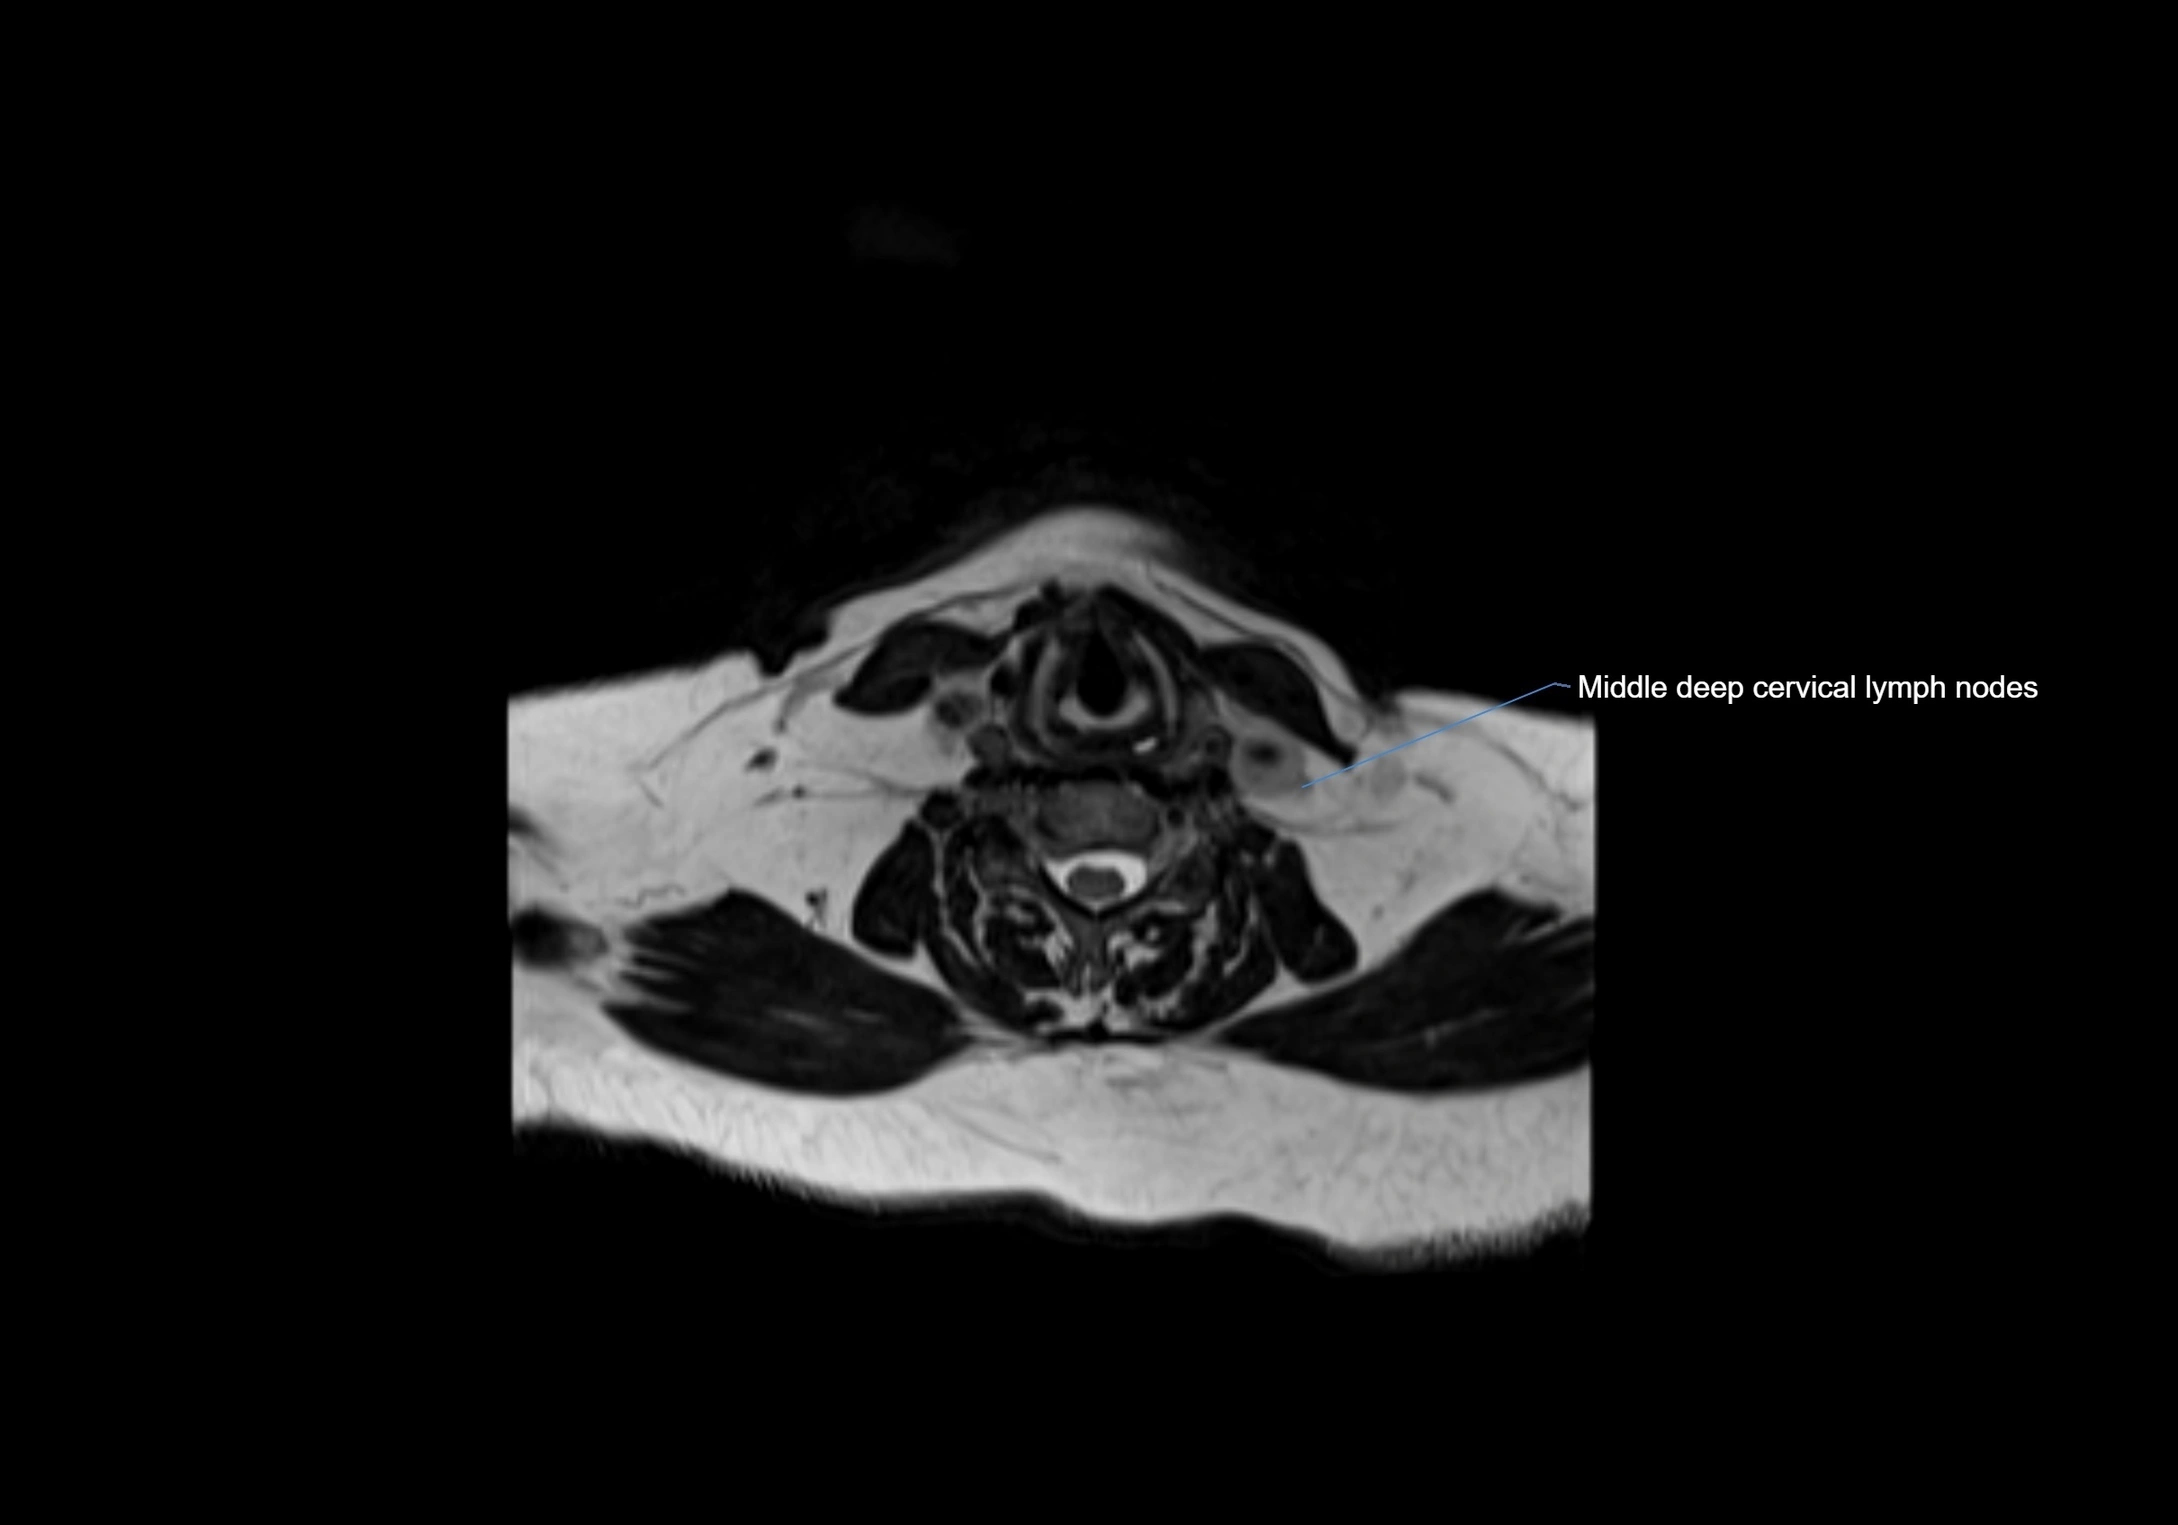

Accessory lymph nodes

Accessory lymph nodes are small, secondary lymph nodes located along the main facial and cervical lymphatic chains, often adjacent to primary lymph nodes, such as preauricular, submandibular, or occipital nodes. They are typically less than 5 mm in diameter, embedded within subcutaneous fat or connective tissue, and may be variable in number and location. These nodes provide additional filtration and immune surveillance for lymph collected from the face, scalp, and neck regions. Accessory lymph nodes are usually non-palpable in healthy individuals but may enlarge in response to infection, inflammation, or metastasis, making them clinically significant.

Location

• Found along primary lymph node chains, including preauricular, submandibular, parotid, and occipital regions

• Embedded in subcutaneous fat or superficial fascia, often lateral or posterior to primary nodes

• Variable in number; may occur unilaterally or bilaterally, depending on individual anatomy

MRI images

image